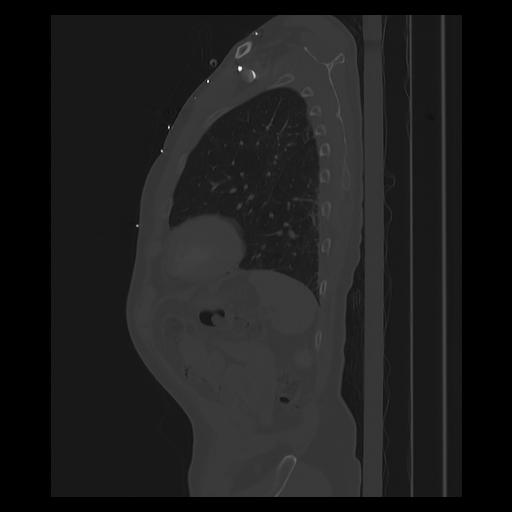

33 PULMON,CE,Sagittal,3.000,PULMON,Sagittal,